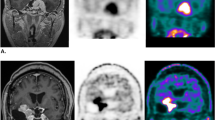

Examples of high and low concordance of Gd-enhanced and 11C-MET accumulation regions are shown in Fig. 5. In a 51-year-old man with a Grade 3 tumor (Fig. 5a), DSC (Gd, T/N 1.3), (Gd, T/N 2.0), (Gd, P-E) were 0.41, 0.77, 0.62, respectively; and JI (Gd, T/N 1.3), (Gd, T/N 2.0), (Gd, P-E) were 0.26, 0.63, 0.46, respectively; with r = 0.58 for the pixel values from MRI and PET. In a 36-year-old woman with a Grade 4 tumor (Fig. 5b), DSC (Gd, T/N 1.3), (Gd, T/N 2.0), (Gd, P-E) were 0.37, 0.85, 0.41, respectively; and JI (Gd, T/N 1.3), (Gd, T/N 2.0), (Gd, P-E) were 0.23, 0.74, 0.26, respectively; with r = 0.004 for the comparison of MRI and PET pixels.

Examples of high and low concordance between Gd-enhanced and 11C-MET accumulation regions. A A 51-year-old man with a Grade 3 tumor. B A 36-year-old woman with a Grade 4 tumor. a Gd-enhanced MRI (red: CTV (Gd)). b 11C-MET PET (blue: CTV (T/N 1.3), green: CTV (T/N 2.0), purple: CTV (P-E)). c CTV contour overlaid on treatment-planning CT. d Correlation coefficient for pixel values in MRI and PET (color figure online)